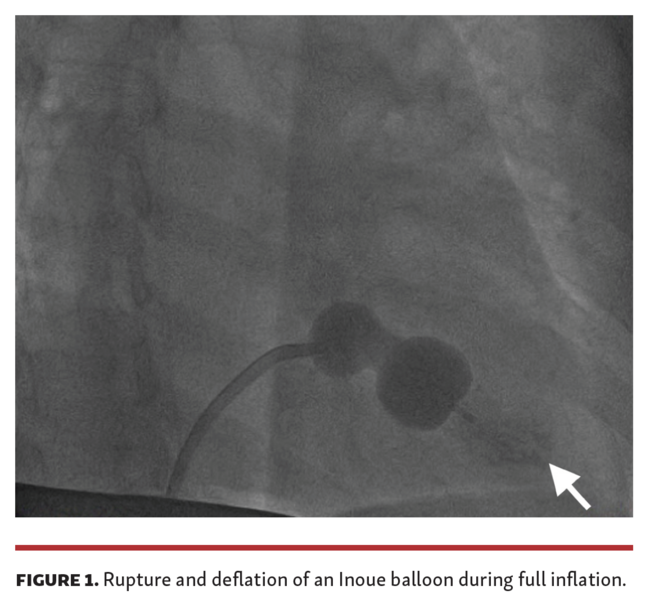

After informed consent, she was taken for percutaneous balloon mitral valvotomy. The 26 mm reused Inoue balloon (Toray Industries) was prepared for 25 mm using the formula height (in cm)/10 + 10. During full inflation of the Inoue balloon, the balloon got ruptured and deflated (Figure 1 and Video 1). There were no complications and the procedure was completed with a new 26 mm Inoue balloon. The mitral valve area was increased to 1.5 cm2 and the mean left atrial pressure decreased from 40 mm Hg to 12 mm Hg (normal is 8 mm Hg).